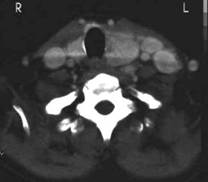

Femeie de 70 ani. Disfonie progresiva prin

paralizie de recurent drept. Nodul voluminos (35 x 25 x 43 mm, 19 cc) care ocupa

aproape complet lobul drept, neomogen, hipoecogen, cu arie anterioara

hipoecogena. Lob stang nevizuzlizat (probabil agenezie). Calcitonina =

820 pg/ml. (v.n. <10pg)

CEA= 638 ng/ml (v.n. <8 ng).

Examen citologic prin citoaspiratie: carcinom midolar cu celule spindle.

CT – aceeasi pacienta – agenezie lob stang